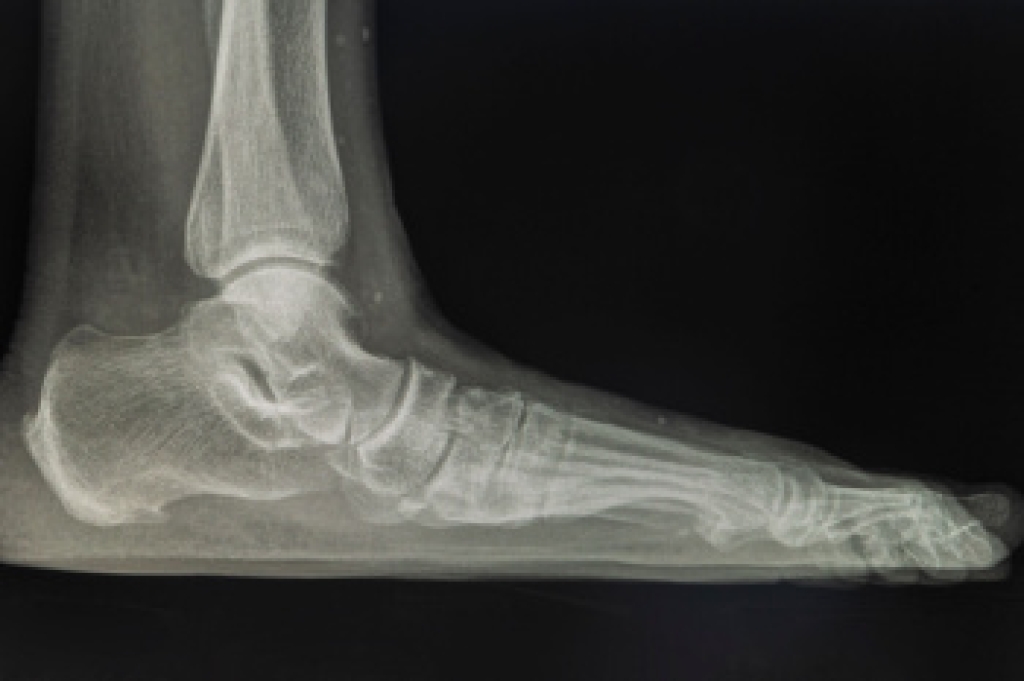

Sever’s disease is also known as calcaneal apophysitis, which is a medical condition that causes heel pain I none or both feet. The disease is known to affect children between the ages of 8 and 14.

Sever’s disease occurs when part of the child’s heel known as the growth plate (calcaneal epiphysis) is attached to the Achilles tendon. This area can suffer injury when the muscles and tendons of the growing foot do not keep pace with bone growth. Therefore, the constant pain which one experiences at the back of the heel will make the child unable to put any weight on the heel. The child is then forced to walk on their toes.